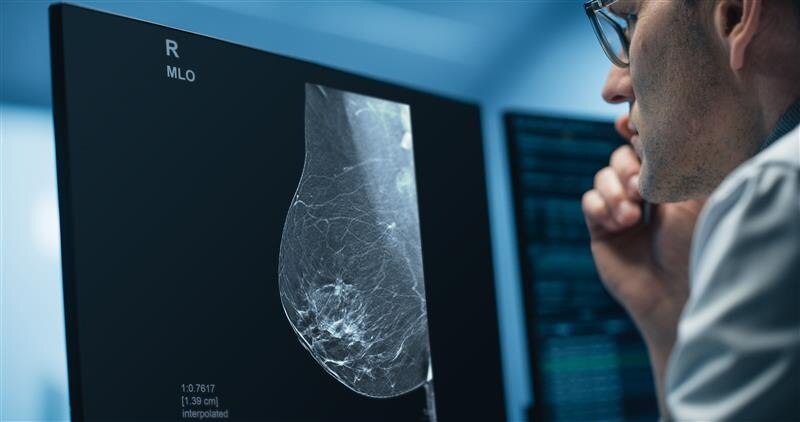

Pristina Recon DL

GEHC announced that it has received FDA Premarket Authorization for Pristina Recon DL.

Nov 26, 2025

Pristina Via

Download